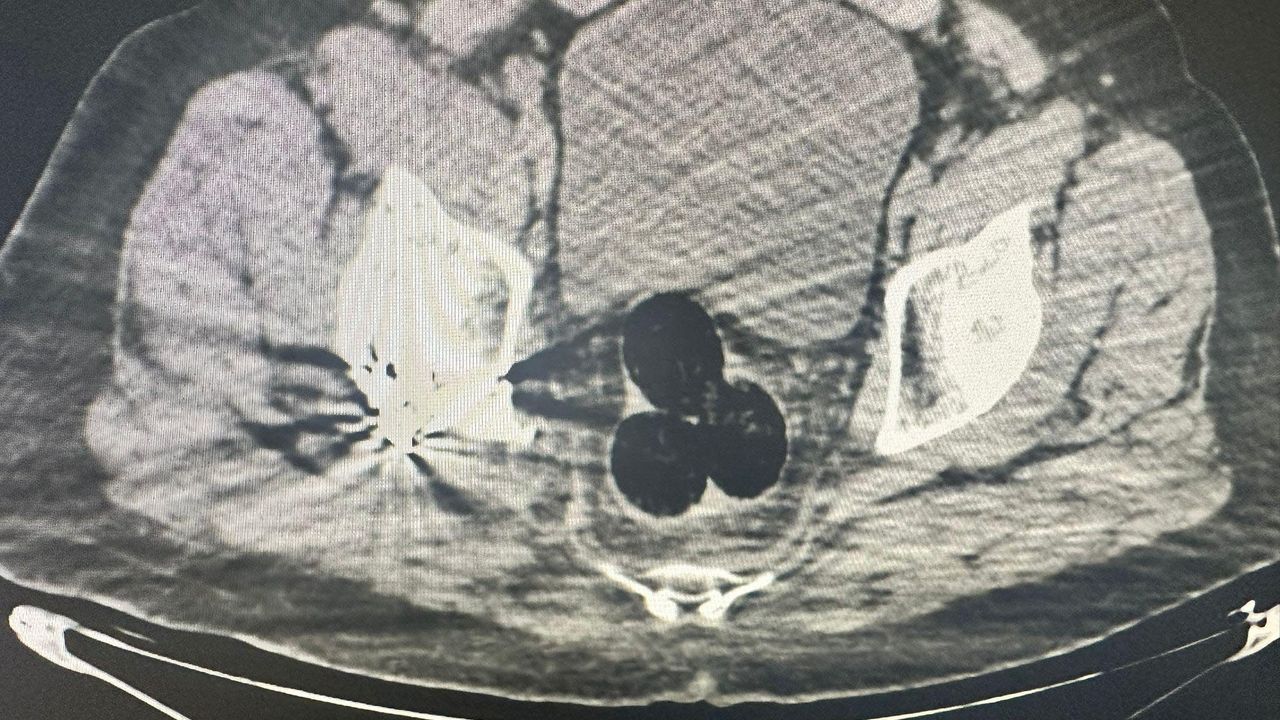

Iğdır Emniyet Müdürlüğü Narkotik Suçlarla Mücadele Şube Müdürlüğü ekiplerince, İran'dan ülkeye giren bir kişi, şüphe üzerine hastaneye götürüldü. Burada yapılan radyolojik görüntülemede şüphelinin makatında 3 parça halinde yabancı cisim saptandı. Hastanede yapılan operasyonla çıkarılan 3 pakette 130 gram metamfetamin ele geçirildi. Şüpheli gözaltına alındı, soruşturma kapsamında polis, bu kişiyle bağlantılı olduğu ve aldıkları uyuşturucuyu Iğdır'da kullanıcılara sattığı tespit edilen 2 şüpheliyi daha yakaladı. 47 gram daha metamfetamin ele geçirirken şüpheliler, emniyetteki işlemlerinin ardından sevk edildikleri adliyede çıkarıldıkları mahkemede tutuklandı.